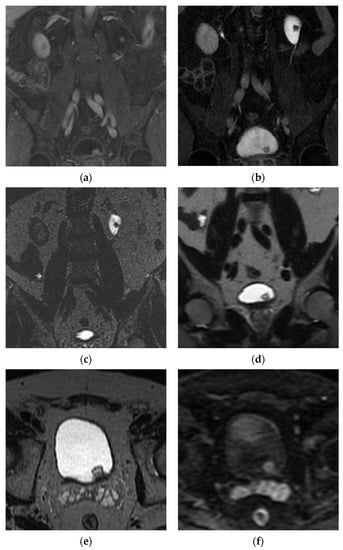

5.2. Magnetic Resonance Imaging (MRI)

- Panebianco, V.; Narumi, Y.; Altun, E.; Bochner, B.H.; Efstathiou, J.A.; Hafeez, S.; Huddart, R.; Kennish, S.; Lerner, S.; Montironi, R.; et al. Multiparametric Magnetic Resonance Imaging for Bladder Cancer: Development of VI-RADS (Vesical Imaging-Reporting and Data System). Eur. Urol. 2018, 74, 294–306. [Google Scholar] [CrossRef] [PubMed]

| Score | Description |

|---|---|

| T2WI Score Structural category (SC) | Muscularis propria is T2 hypointense Tumor is T2 intermediate in signal |

| SC 1 | Uninterrupted low signal intensity (SI) line representing the muscularis propria. Lesion < 1 cm Exophytic tumor

|

| SC 2 | Uninterrupted low signal intensity (SI) line representing the muscularis propria Lesion > 1 cm Exophytic tumor with stalk +/− high SI thickened inner layer, when present. Sessile/broad-based tumor with high SI thickened inner layer, when present |

| SC 3 | Lack of category 2 findings with no clear disruption of low SI muscularis propria. Associated presence of

| SC 4 | Intermediate SI tumor interrupts low SI line (muscularis propria) |

| SC 5 | Intermediate SI tumor extends into extravesical fat |

| DCE Score Contrast-enhanced category (CE) | Tumor and inner layer enhance early Muscle should not enhance early |

| CE 1 | No early enhancement of muscularis propria |

| CE 2 | No early enhancement of muscularis propria with early enhancement of inner layer |

| CE 3 | Lack of category 2 findings with no clear disruption of muscularis propria |

| CE 4 | Early enhancing tumor extends into muscularis propria |

| CE 5 | Early enhancing tumor extends to entire bladder wall and to extravesical fat |

| DWI/ADC score Diffusion weighted category (DW) | Tumor is hyperintense on DWI, hypointense on ADC Muscularis propria is intermediate SI on DWI Stalk and inner layer are low SI on DWI |

| DW 1 | Intact intermediate SI muscularis propria on DWI Lesion < 1 cm |

| DW 2 | Intact intermediate SI muscularis propria on DWI Lesion > 1 cm |

| DW 3 | Lack of category 2 findings with no clear disruption of muscularis propria |

| DW 4 | Tumor (high SI on DWI/low SI on ADC) extends into muscularis propria |

| DW 5 | Tumor (high SI on DWI/low SI on ADC) extends to entire bladder wall and extravesical fat |

| Final Score | T2WI helpful especially for VI-RADS 1-3 DWI and DCE are dominant sequences for risk estimate, especially for VI-RADS 4-5 |

| VI-RADS 1 | Muscle invasion highly unlikely SC 1, CE 1, and DW 1 |

| VI-RADS 2 | Muscle invasion unlikely SC 2 + CE 2 and DW 2 SC 3 + CE 2 and DW 2 |

| VI-RADS 3 | Muscle invasion equivocal SC 3 + CE 3 and/or DW 3 (or below) |

| VI-RADS 4 | Muscle invasion likely SC 4 + CE 4 and/or DW 4 (or below) SC 5 + CE 4 and/or DW 4 (or below) |

| VI-RADS 5 | SC 4 + CE 5 and/or DW 5 SC 5 + CE 5 and/or DW 5 |